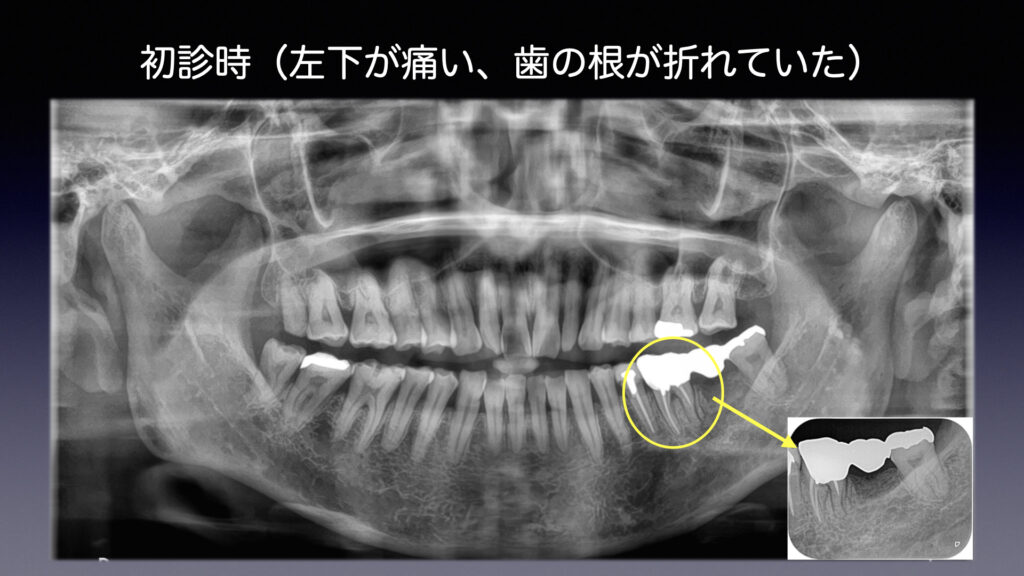

初診から治療終了までの流れ

② 過去との比較

治療した当初の状態と比較し、

変化が起きていないかを丁寧に確認します。